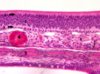

what is this image of?

olfactory epithelium

1

tall columnar supportive cells

2

olfactory neurons (bipolar)

3

basal cells